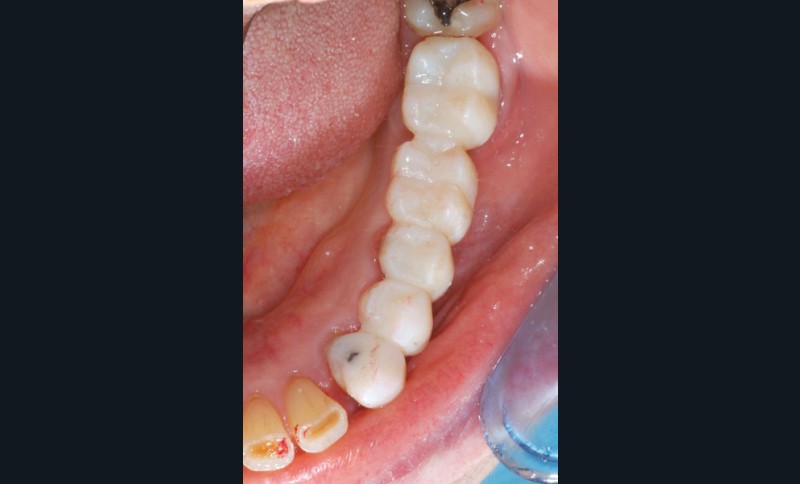

Le bridge 24-26 céramométallique et la couronne unitaire sur 27 sont réalisés. Les piliers CFAO sont transvissés sur les implants, puis les éléments céramo-métalliques sont posés. Le résultat montre un parfait respect du projet prothétique en fonction de la courbe occlusale obtenue avec le bridge transitoire réalisé avec le ProtempTM 4 et une adaptation parfaite.